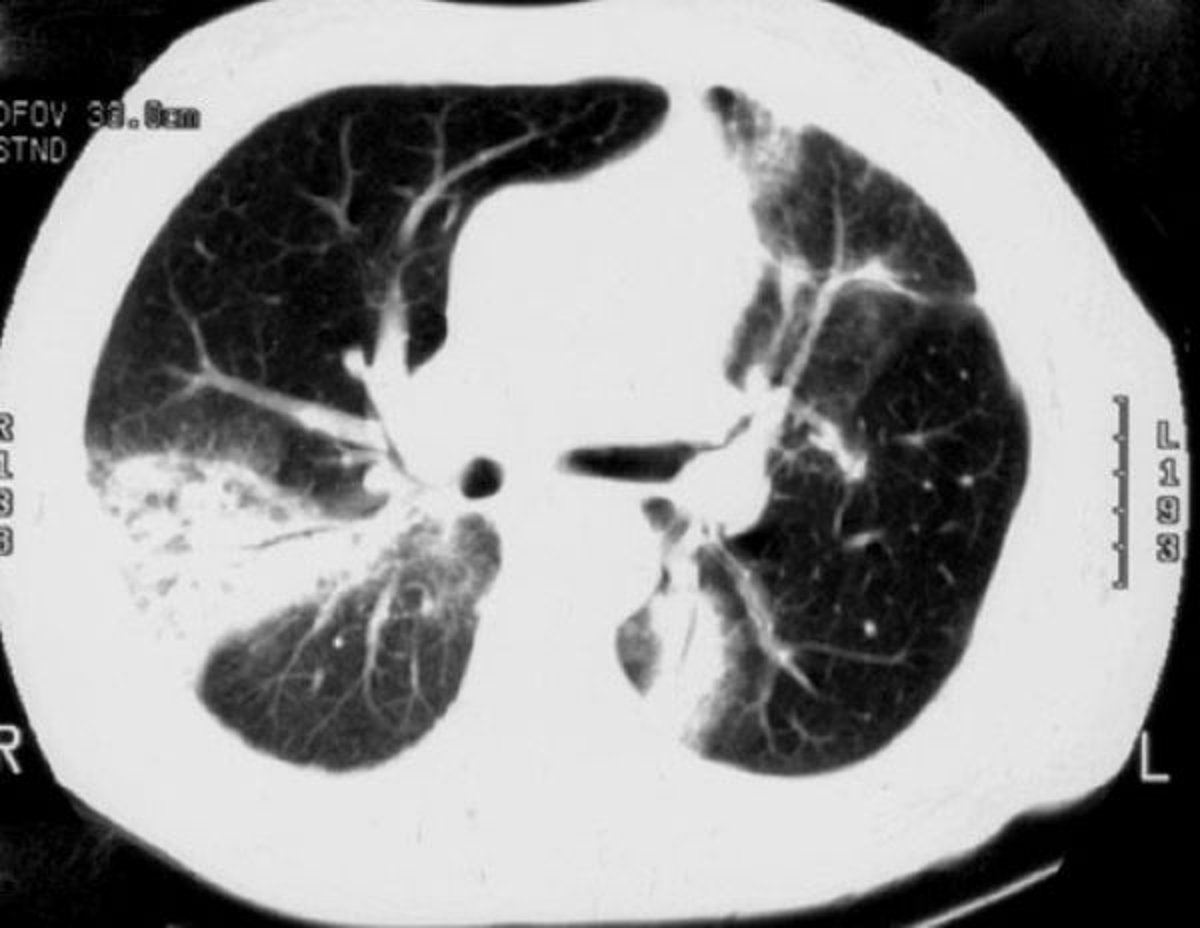

特発性器質化肺炎

高分解能CTで,斑状の気腔の浸潤影(consolidation),すりガラス陰影,小結節状陰影,ならびに気管支壁の肥厚および拡張(air bronchogram)がみられる。

Image courtesy of Talmadge E.King, MD.